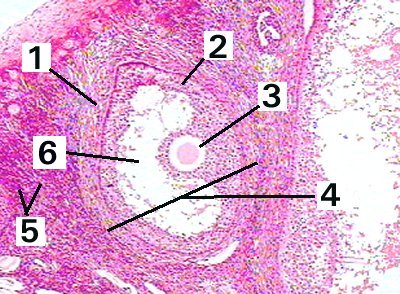

2. Granulosa cells

3. Ovum

4. Ovarian follicle

5. Stroma

6. Follicular antrum

| Fig 89-001 | |

| This is a low magnification of a mature ovarian follicle demonstating the different layers and structures. | |

1. Follicular theca 2. Granulosa cells 3. Ovum 4. Ovarian follicle 5. Stroma 6. Follicular antrum |